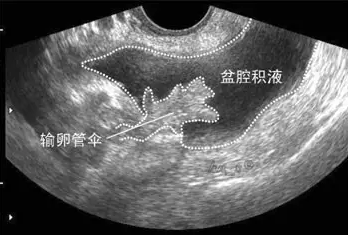

盆腔積液大多是盆腔存在炎性滲出物,常表現(xiàn)為小腹下墜、脹痛,腰酸腰痛、月經(jīng)紊亂、不孕等,那具體盆腔積液是怎么引起的呢?盆腔積液是怎么回事?盆腔積液的危害有哪些?盆腔積液的產(chǎn)生主要可分為生理性因素和病理性因素兩種。

生理性盆腔積液是指正常的盆腔積液,不需要治療。人體的盆腔、腹腔并不是干巴巴的一塊「土地」,腹膜、大網(wǎng)膜、腸管等都會(huì)分泌一些液體,這些液體通常起到潤(rùn)滑和保護(hù)盆腹腔器官和組織的作用。盆腔積液可通過(guò) B 超檢查觀察到,如果積液的深度小于 3 cm,沒(méi)有其他不舒服的癥狀,通常是不需要處理的。

不孕是盆腔積液最常見(jiàn)的癥狀。如果盆腔炎導(dǎo)致輸卵管堵塞,就會(huì)出現(xiàn)不孕。